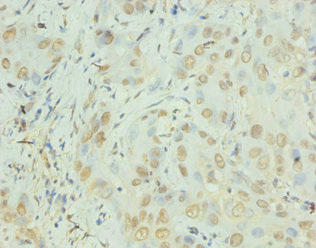

Immunohistochemistry of paraffin-embedded human liver cancer using CSB-PA08327A0Rb at dilution of 1:100